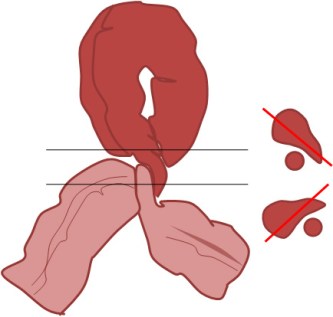

SIGNO DEL PICO

Signo de vólvulo y otras causas de obstrucción intestinal en asa cerrada, que inicialmente se describió en el estudio baritado (enema opaco). Se refiere a la estenosis fusiforme que se dirige al punto de torsión (flecha roja en la radiografía y flecha negra en el esquema). En caso de que el contraste atraviese la estenosis y exista una disminución de la luz en el segmento proximal de la torsión, la imagen obtenida recuerda a la de dos pájaros con sus picos juntos.

La imagen muestran el Signo del pico en un paciente con un vólvulo de sigma.

Aunque lo hemos incluido dentro de los signos de colon, este signo también es visible en las obstrucciones en asa cerrada de intestino delgado.

Inicialmente descrito en el enema opaco, en la TC también es visible este signo y no solamente en el asa eferente (como ocurre en el enema opaco, donde este asa se rellena retrógradamente) sino también en el aferente.

Existe otro Signo del pico en la achalasia, afectando al esófago distal, ya descrito en la sección correspondiente (ABDOMEN/Tubo digestivo/Esófago).